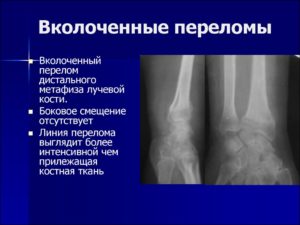

- Вколоченные, при которых костные отломки входят («вколачиваются») друг в друга;

Повреждение может быть оскольчатым, вколоченным, с наличием сместившихся отломков или без смещения.

- При вколоченном переломе имеет место вклинивание одного костного отломка в другой в результате приложения силы перпендикулярно оси конечности. При этом происходит раздробление проникающих друг в друга отломков и укорочение конечности.

Наиболее благоприятный вариант повреждения – трещина. Трещина – это линия излома, которая не проникает на всю толщу костной структуры. При вколоченной травме также отсутствует смещение отломков, но этот вариант требует более длительной реабилитации.